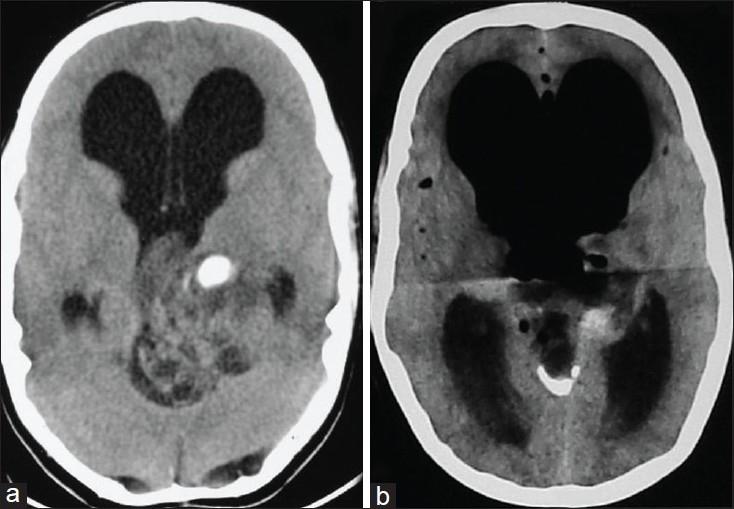

Occurrence of tension pneumoventricle (symptomatic intraventricular air) can result in rapid clinical deterioration in an otherwise stable patient. It is a rare clinical entity, mentioned in relation to cerebrospinal fluid (CSF) diversion procedures, during the late postoperative period. We present a patient with posterior third ventricular tumor who underwent excision by midline suboccipital craniotomy in sitting position. Neurological status of the patient deteriorated rapidly in the immediate postoperative period owing to development of tension pneumoventricle. The condition improved after twist-drill burr-hole evacuation of air under water-seal. Pre-existing gross hydrocephalus, exploration of third ventricle in sitting position, and residual tumor in third ventricle were possibly the factors responsible for this complication.

张力性脑室积气(有症状的脑室内积气)的出现可导致原本病情稳定的患者临床状况迅速恶化。它是一种罕见的临床情况,在术后晚期与脑脊液(CSF)分流手术相关。我们报告一名患有第三脑室后部肿瘤的患者,该患者在坐位下行枕下中线开颅肿瘤切除术。术后即刻患者的神经状况因张力性脑室积气的发生而迅速恶化。在水封下通过钻孔引流积气后病情改善。术前存在的严重脑积水、坐位下对第三脑室的探查以及第三脑室内的残留肿瘤可能是导致该并发症的因素。